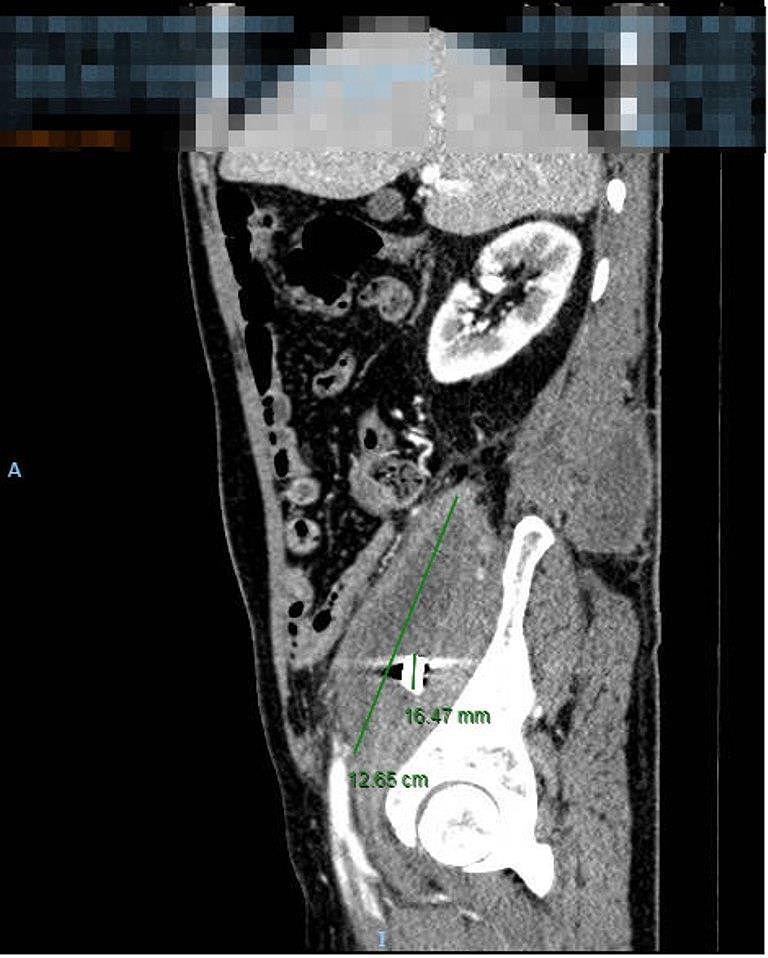

Qua thăm khám toàn diện, chụp cắt lớp điện toán vùng bụng, các bác sĩ phát hiện bệnh nhân có một ổ áp xe to tại vùng cơ thắt lưng chậu phải, ổ áp xe đã lan ra sau lưng. Sâu bên trong ổ áp xe có ghi nhận hình ảnh nghi ngờ của mảnh kim loại, tương ứng với mảnh đạn từng kẹt lại trong người bệnh nhân.

Kết quả xét nghiệm máu cho thấy tình trạng bạch cầu máu của ông K. tăng cao, dấu hiệu nhiễm trùng nặng. Với chẩn đoán áp xe lớn cơ thắt lưng chậu bên phải nghi do mảnh đạn, các BS khoa Ngoại tiêu hóa của BV đã chỉ định mổ cấp cứu cho ông K.